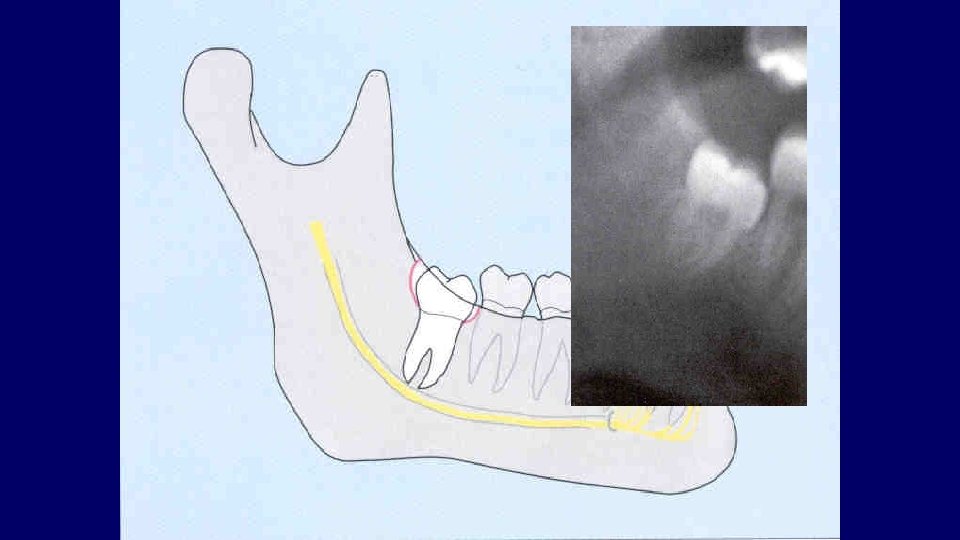

Types of impaction • Vertical • Mesioangular • Distoangular • Horizontal • Transverse

(2) Depth of impaction

Pell & Gregory Classification • Based on the amount of tooth covered by the anterior border of the ramus • The depth of the impaction relative to the adjacent tooth

Pell & Gregory • Depth of Impaction – Mandibular Class A Class B Class C

Pell & Gregory